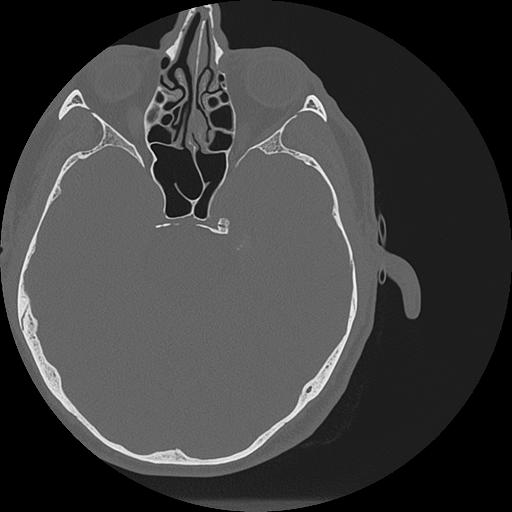

7 HUESO,,Vol,0.5,HUESO,,